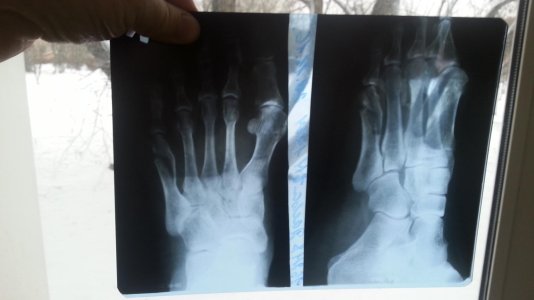

• IMG_20161224_170558.jpg

IMG_20161224_170558.jpg

238,5 КБ · Просмотры: 263